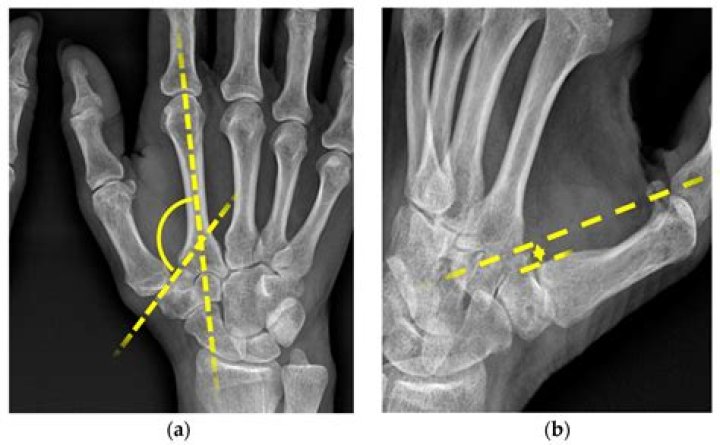

Introduction. Dorsal subluxation is a typical finding of thumb carpometacarpal (CMC) osteoarthritis, which indicates ligament laxity and instability of the joint. 1 2. Ligament reconstruction, therefore, is one of the surgical treatments for painful thumb CMC joints.